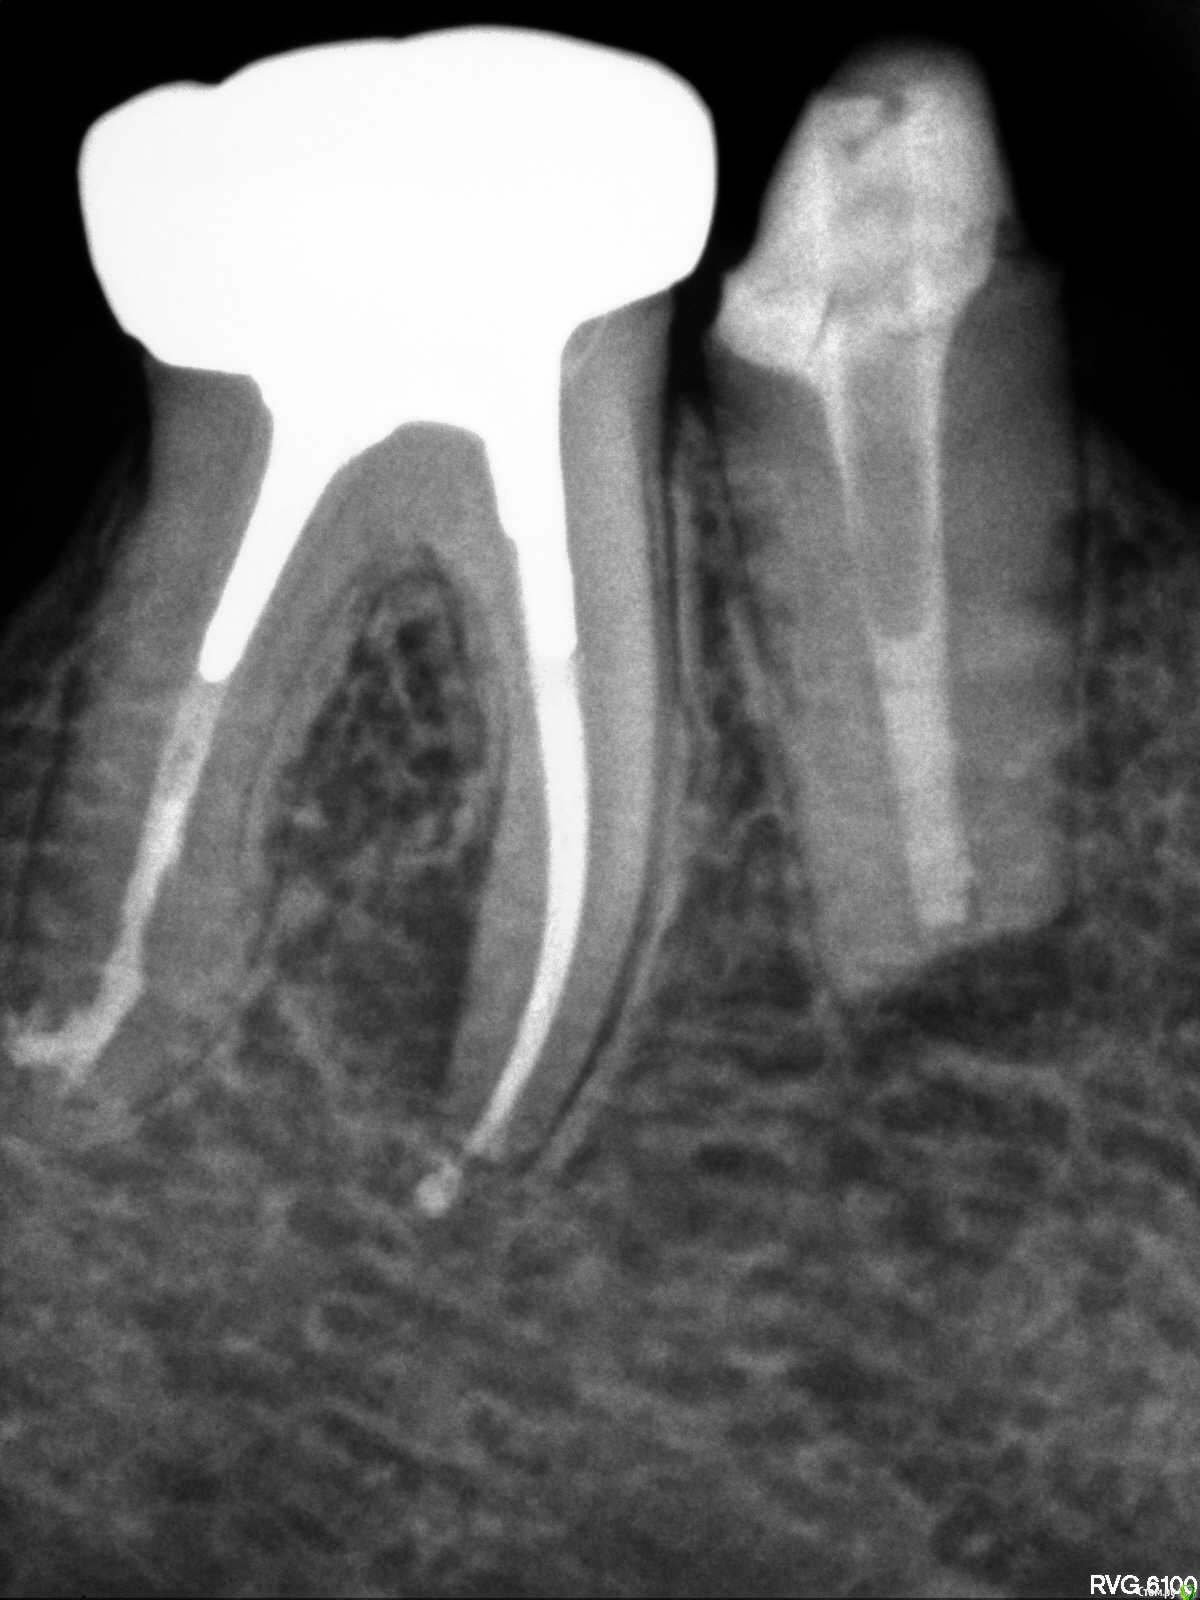

Placeforastep Опубликовано 11 февраля, 2021 Поделиться Опубликовано 11 февраля, 2021 Добрый день! Подскажите пожалуйста, есть ли на корне периодонтит ? Ссылка на комментарий

Placeforastep Опубликовано 13 февраля, 2021 Автор Поделиться Опубликовано 13 февраля, 2021 Здравствуйте, что Вас беспокоит?Беспокоит хроническая боль/зуд в районе этих двух зубов (5 и 6 нижние зубы). Усиливается к вечеру , ночи и особенно сильно по утрам . Так уже 6 лет. Это долгая история. Просто хотел получить второе мнение есть ли на 6 зубе признаки периодонтита. Ссылка на комментарий

annda Опубликовано 14 февраля, 2021 Поделиться Опубликовано 14 февраля, 2021 (изменено) Не походит на боли при периодонтите. Изменено 14 февраля, 2021 пользователем annda 1 Ссылка на комментарий

red_butler Опубликовано 15 февраля, 2021 Поделиться Опубликовано 15 февраля, 2021 Ничего плохого на rg не увидел Ссылка на комментарий